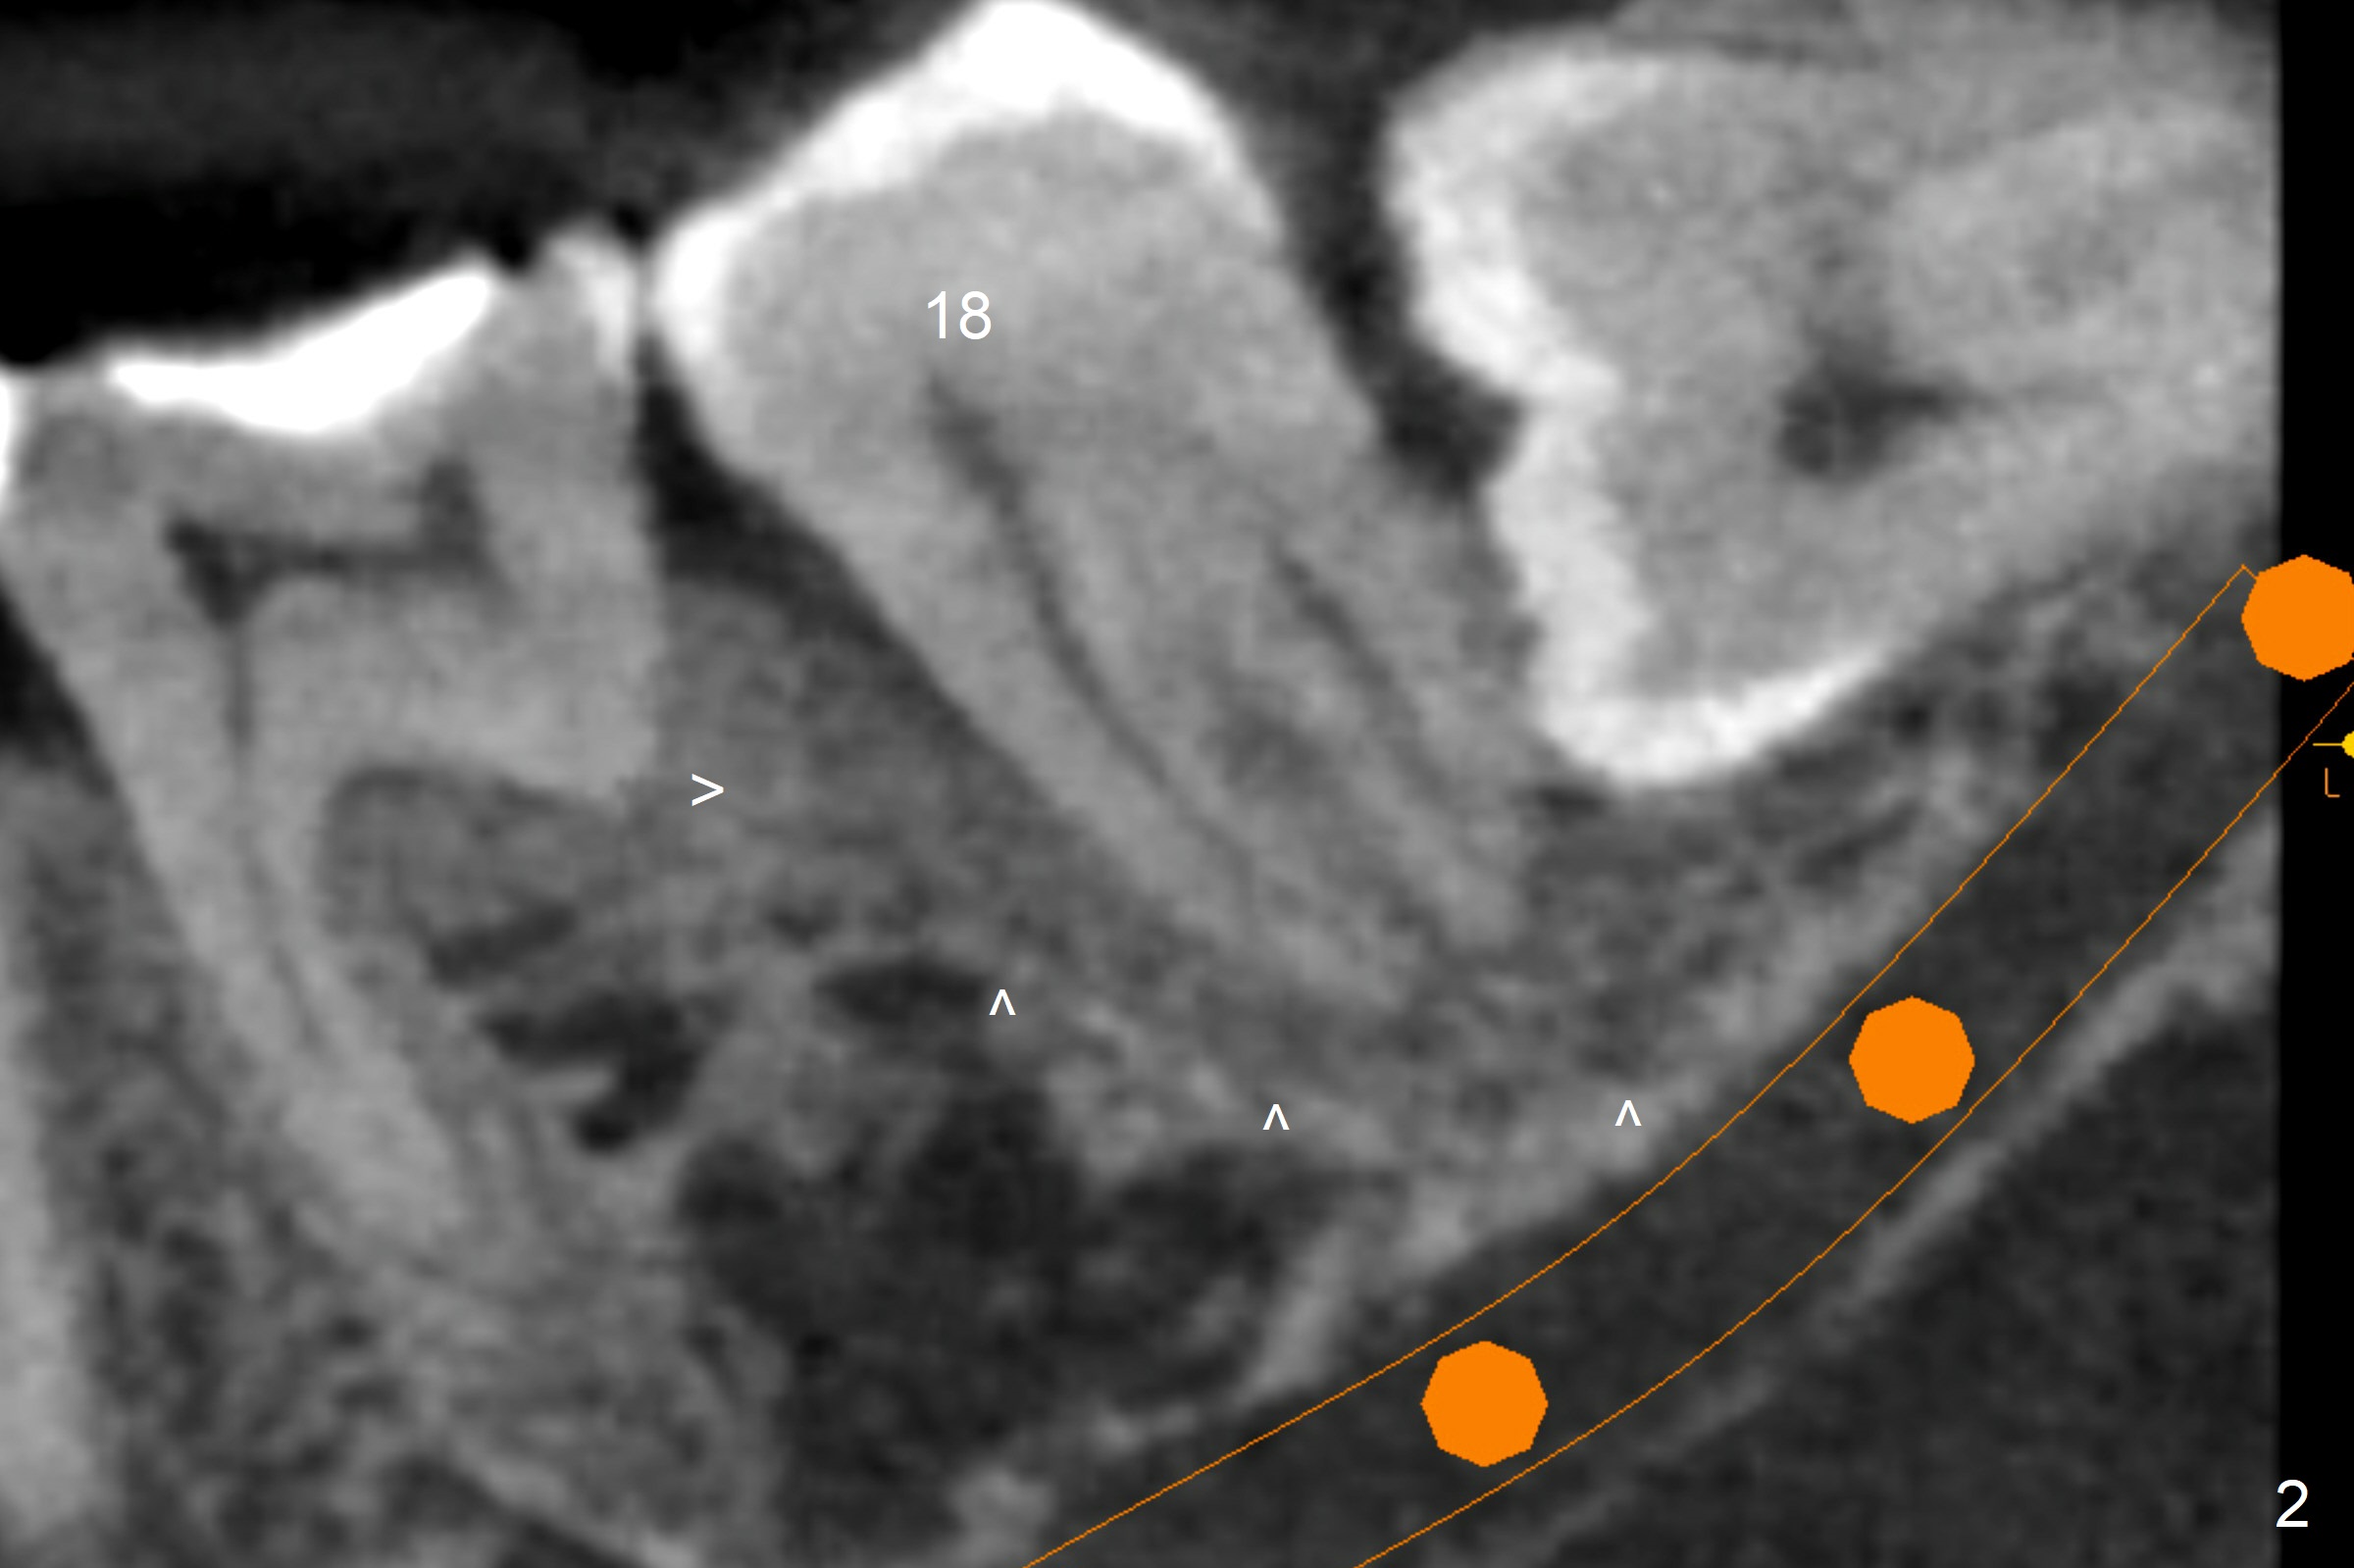

A 40-year-old man removes food debris from the lower left area, probably between #17 and 18, using Water Pik. Initially it looks as if the bone loss lingual (Fig.1 (CBCT with 3 sections) L) to #18 is derived from #17 (red curved arrow). Closer look shows generalized thickened periodontal ligament space at #18 (Fig.2 arrowheads). The patient requests extraction of the tooth #17; the tooth #18 seems non-salvageable. When an immediate implant is placed in the middle of the socket (Fig.3,4 (coronal section)), there is limited amount of the native bone to stabilize the implant (~1 mm). In contrast, there is approximately 5 mm of the native bone for primary stability if the implant is placed in the mesial slope of the fused socket (Fig.5 yellow dashed line). The implant should be placed buccally (B) to reduce the chance of nerve injury (Fig.4,6).